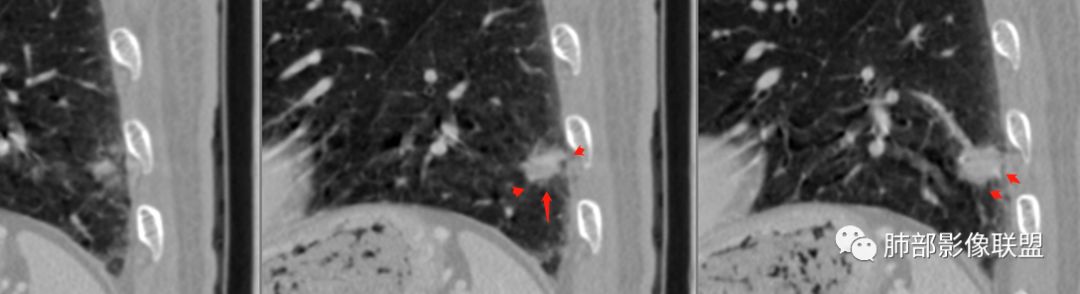

南大分析病例1

南边:

老年男性,因为头部症状来诊,也就是说肺部没症状

胸膜下结节,边界清楚、光滑,边缘稍凹陷,有胸膜牵拉

支气管在门口堵了

一般这类结节,边缘光滑

似有浅分叶

门口支气管堵塞——提示与支气管相关,不支持良性肿瘤

炎性?恶性?

符合炎性的地方:

实性,边缘凹陷,强化均匀

让我们不踏实的地方:

似乎有脐凹征

除了胸膜牵拉,还有短毛刺?血管纠集

支气管在门口堵塞

综合起来看,恶性不能排除。建议穿刺活检,一定要认清楚:我们影像有局限性。

应当说两例患者影像学表现都具有比较明显恶性征象,中老年男性患者,均都没有呼吸系统临床症状。

病例1为胸膜下实性小结节,血管脐凹样出入,可见支气管阻塞。病灶膨隆,部分边缘平直,周围晕征不明显,未见分叶,但可见毛刺及胸膜牵拉,增强后明显强化,老年男性,怀疑新生物尤其是腺癌是有理由的。